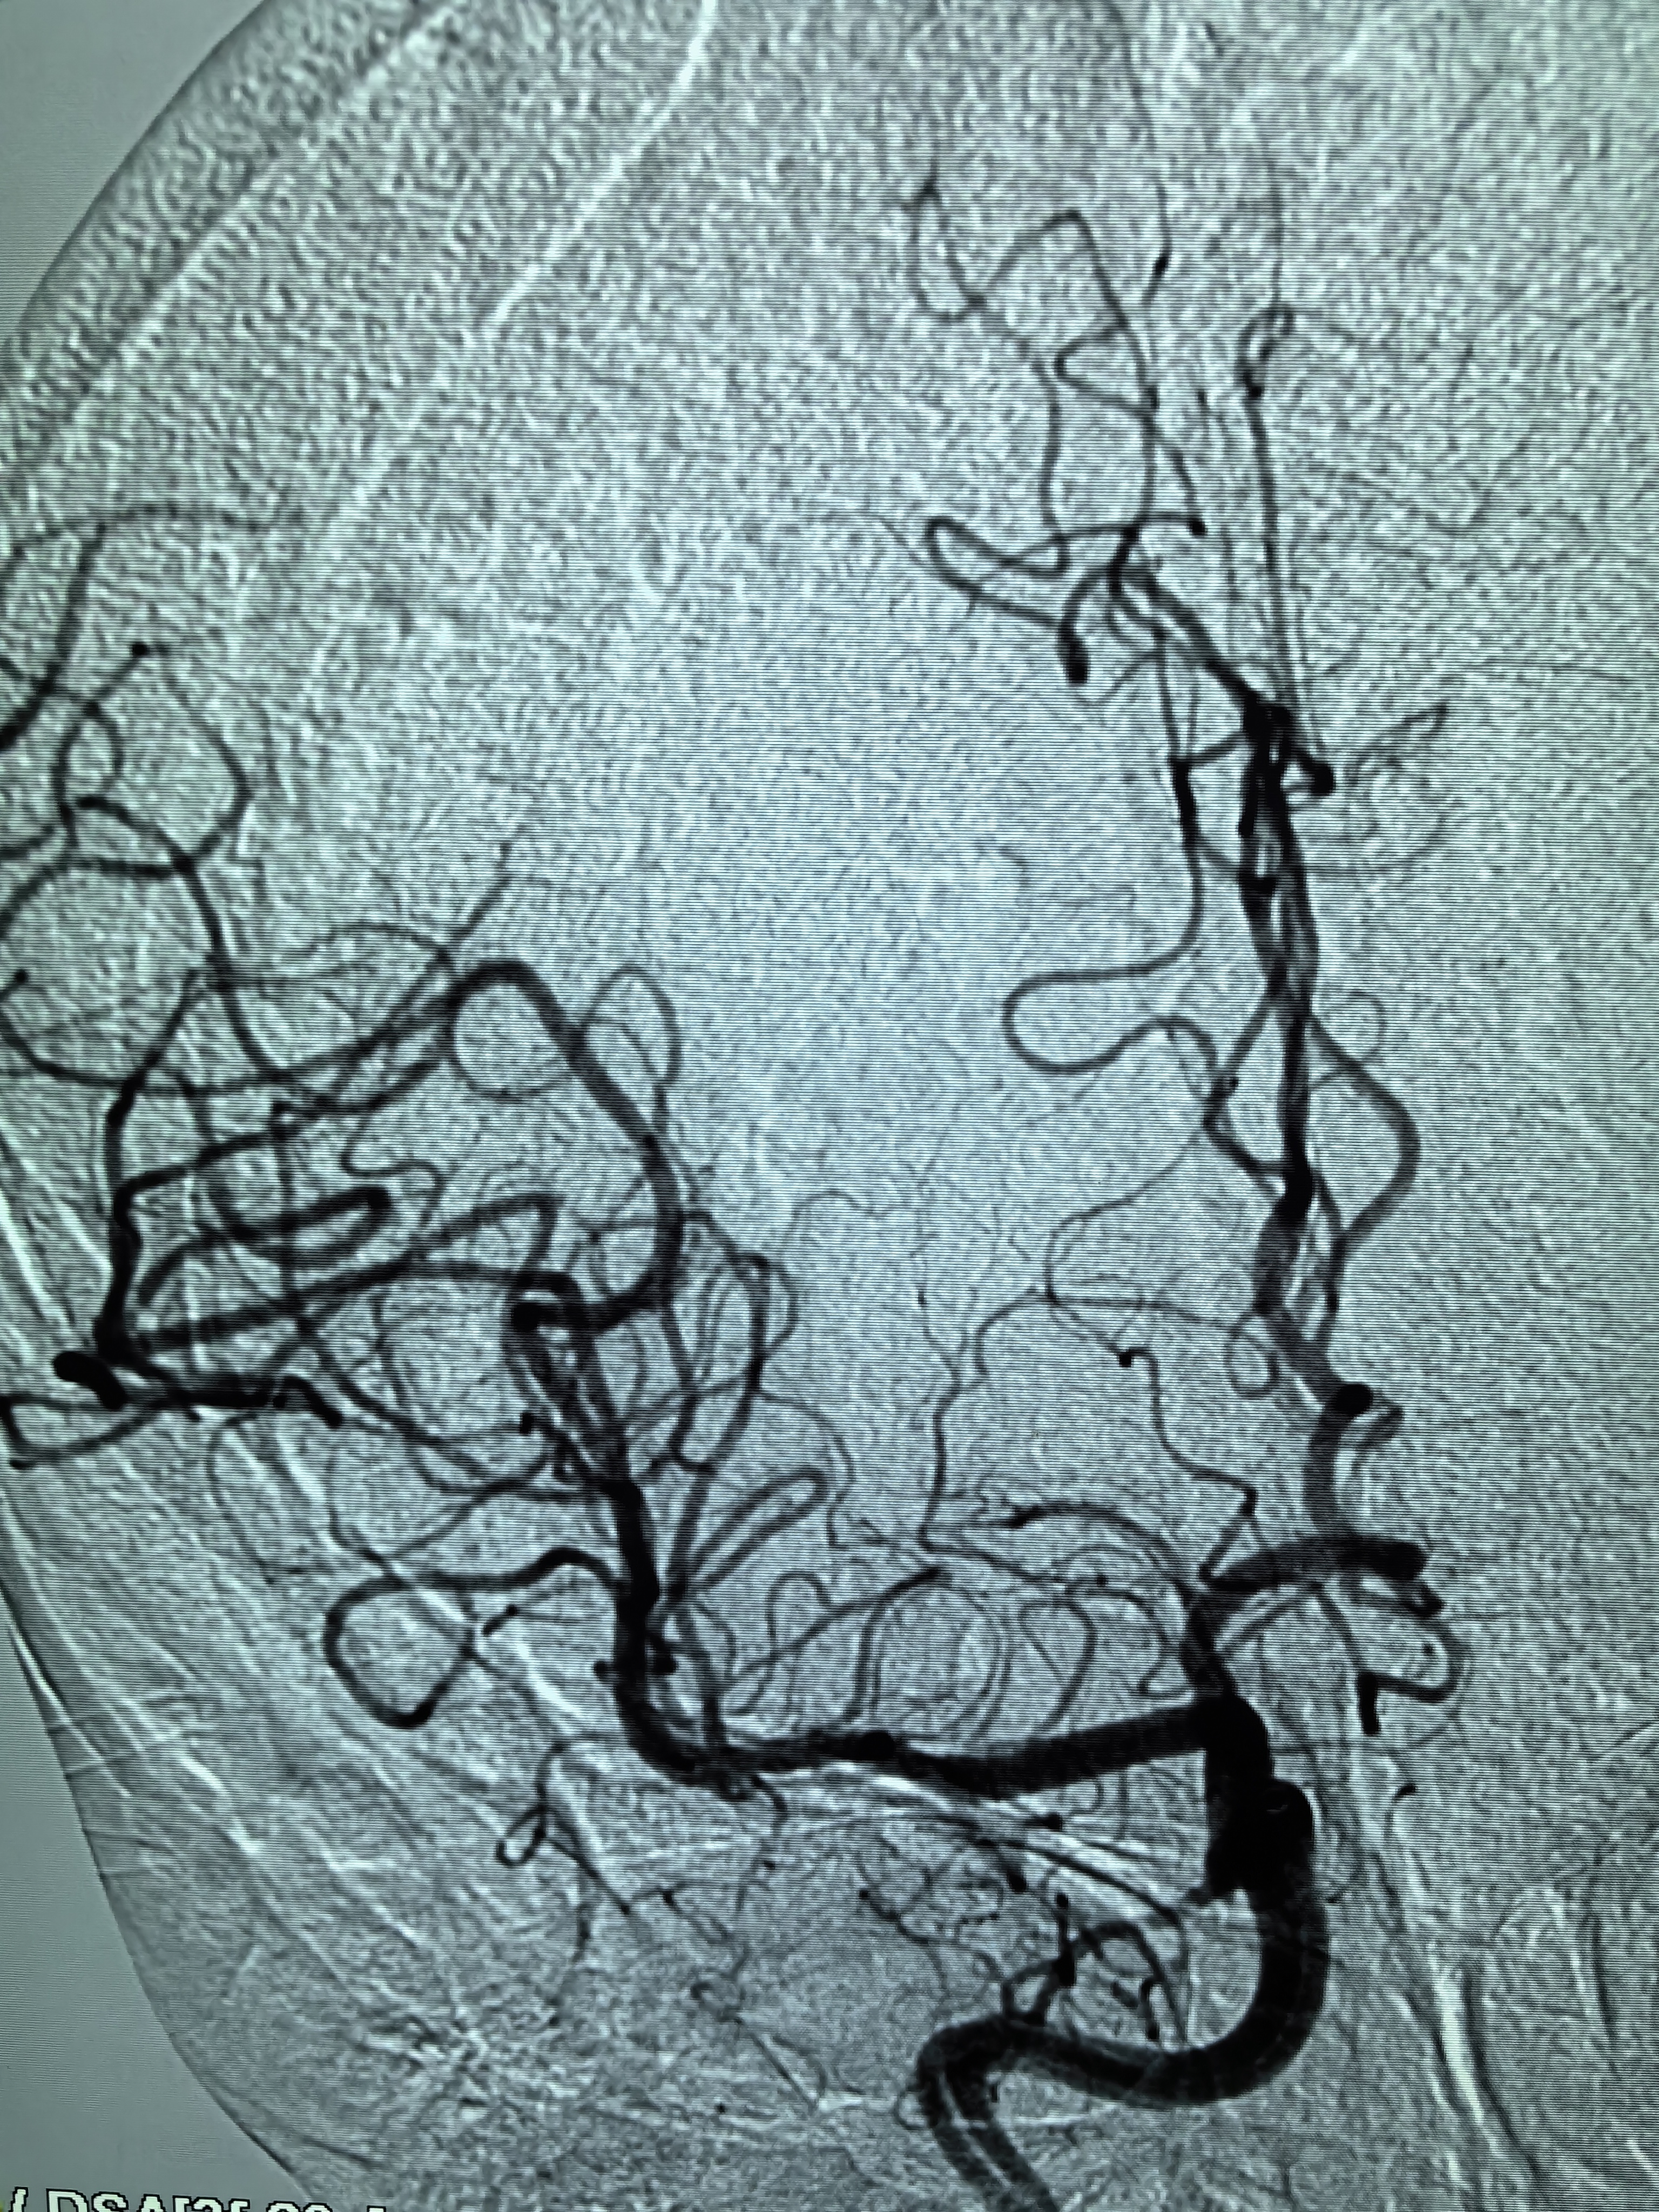

患者术前明确右侧颈内动脉系统栓塞,遂快速建立8F导引导管+CAT6中间导管取栓路径,微导丝携微导管顺利通过病变。